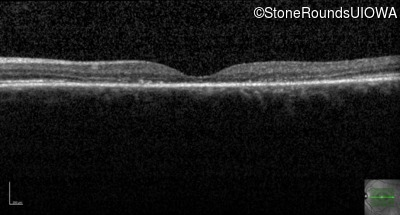

Cone and Cone Rod Dystrophy (IA1b)

Age at visit: 49 years

This 49 year old woman first experienced some loss of central vision in her left eye at age 44.